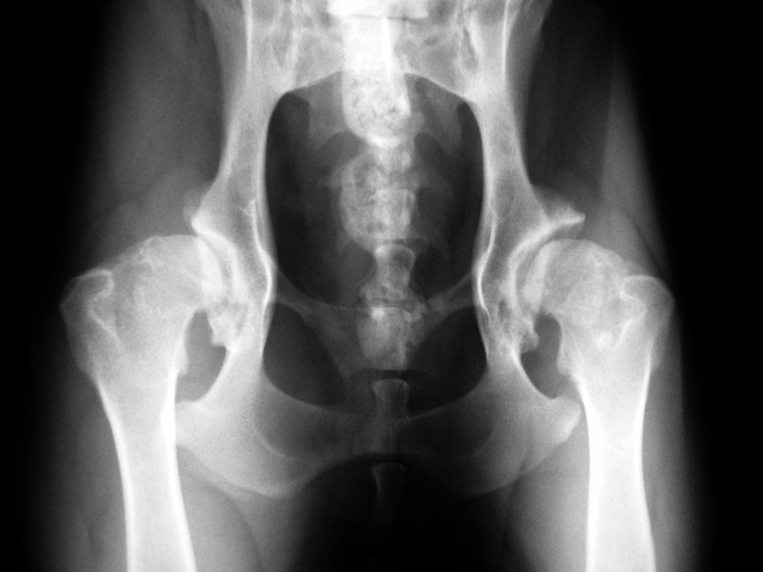

Die Diagnose HD lässt sich anhand von Röntgenaufnahmen des Hüftgelenks stellen. Sichtbare Veränderungen können an der Gelenkspfanne, am Oberschenkelkopf oder an beiden Knochen auftreten. Bei jungen Hunden ist gelegentlich nur ein auffällig lockeres Hüftgelenk zu beobachten, bei dem der Oberschenkelkopf nicht korrekt in der Gelenkspfanne liegt.

Abb. 1: Verschiedene Hüftgelenke, von A, normal bis E, hochgradig dysplastisch (Bildfolge Dr. A. Vezzoni, mit bestem Dank).

Abb. 2: Exzellente Hüftgelenke (Grad A) bei einem 15 Monate alten Labrador Retriever der Blindenführhundeschule Allschwil. Bei beiden Hüftgelenken sitzt der runde Oberschenkelkopf tief in der Pfanne. Der Vorderrand der Pfanne (oben) liegt dem Kopf exakt an, der Gelenkspalt ist schmal, der vordere Pfannenknochen gleichmässig schmal. Durch umfassende Nachzuchtkontrolle mit rigider Auslese der Zuchttiere aufgrund der Qualität der Nachkommen weisen weit über 90% der Hunde der Schule hervorragende Hüftgelenke (und Ellbogengelenke) auf.

Abb. 3: Englischer Setter mit HD Grad C. Der Oberschenkelkopf ist zwar rund, rutscht aber etwas aus der Pfanne. Der vordere Pfannenrand läuft horizontal aus. Solche Hunde neigen im Laufe des Lebens zu Hüfgelenksarthrose.

Abb. 4: 8 Monate alter Mischlingshund mit hochgradiger HD (Grad E). Der Kopf ist kantig, oben abgeflacht und weitgehend aus der Pfanne herausgerutscht, die Pfanne selber oben stark abgeflacht, sogar fliehend. Am Vorderrand der linken Pfanne (im Bild rechts) hat sich eine Randzacke ausgebildet, ein untrügliches Zeichen von schwerer Arthrose.

Abb. 5: Derselbe Hund im Alter von 5 Jahren. Die Oberschenkelköpfe sind nun hochgradig verformt und berühren die Pfannen nur noch knapp. Die Oberschenkelhälse sind massiv verdickt und verformt, die Morganlinien sind als breite Knochenleiste erkennbar. Beide Pfannen sind stark abgeflacht und haben insbesondere rechts hochgradige arthrotische Zubildungen entwickelt.